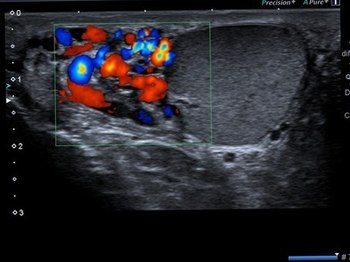

Parotis enfeksiyonlarından en bilineni genellikle çocukluk çağında görülen kabakulaktır. Kabakulak dışında viral ve bakteriyel enfeksiyonlar gelişebilir. Bu durumlarda renkli doppler ultrason tanı açısından önemlidir. Parotisin iyi ve kötü huylu kitleleri mevcuttur. Ultrason incelemesinde parotis kitlesinin şekli, anatomik özellikleri ve doppler inceleme özelliklerine bakılarak tanıya yardımcı olunabilir. Eğer kitle kötü huylu olma potansiyeli taşıyorsa ultrason eşliğinde ince iğne aspirasyon biyopsisi ile patolojik tanı konulabilir. Bir diğer parotis kitlesi sebebi de parotis içinden gelişen lenf nodlarıdır. Genellikle reaktif olan bu lenf nodları (enfeksiyona bağlı) zaman zaman ağrı sebebi olabilir.